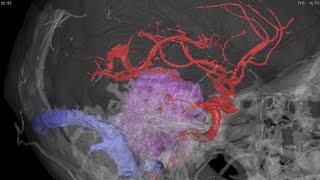

Christian Schiffer: Perspectives of High-Resolution 3D Reconstruction Cysticercosis 3D reconstruction of a patient.

Cysticercosis 3D reconstruction of a patient. 3D reconstruction of BigBrain2: Challenges and Milestones

3D reconstruction of BigBrain2: Challenges and Milestones EDDA 3D Lung Segmentectomy

EDDA 3D Lung Segmentectomy 3D Reconstruction of Giant Parasellar brain tumor

3D Reconstruction of Giant Parasellar brain tumor